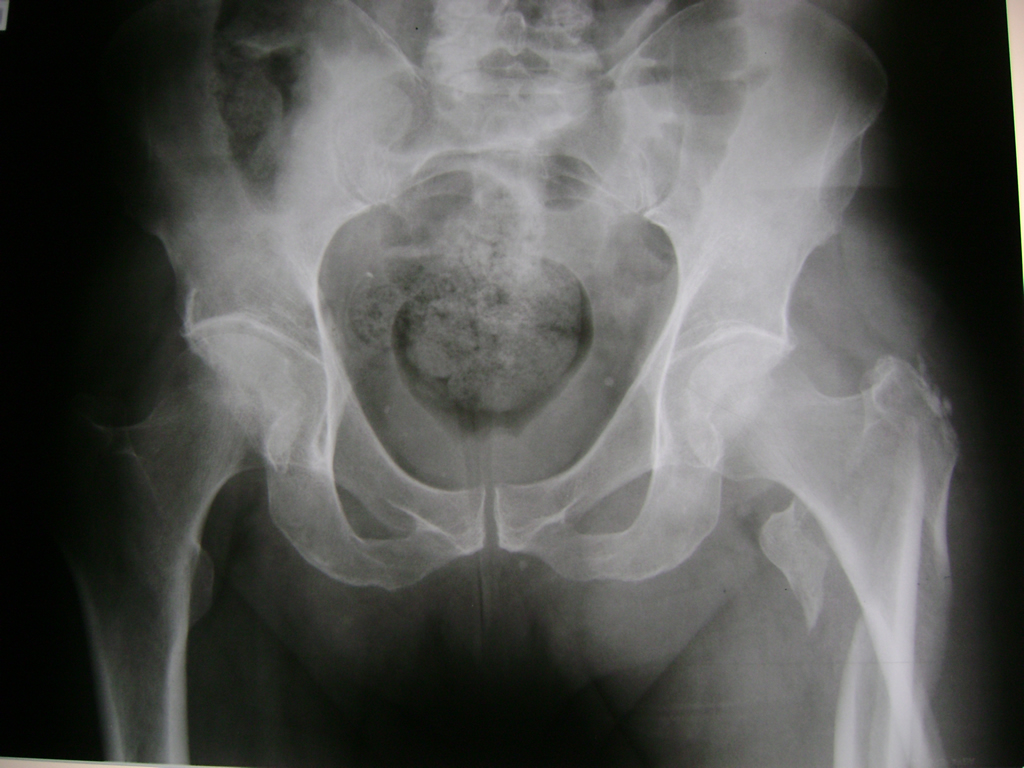

Fémur - Cadera

La cirugía de fractura de cadera se realiza para reparar una ruptura en la parte superior del hueso del muslo. Este hueso se denomina fémur.

Es parte de la articulación coxofemoral. Si una fractura de cadera no recibe tratamiento, es posible que deba permanecer en una silla o en la cama.